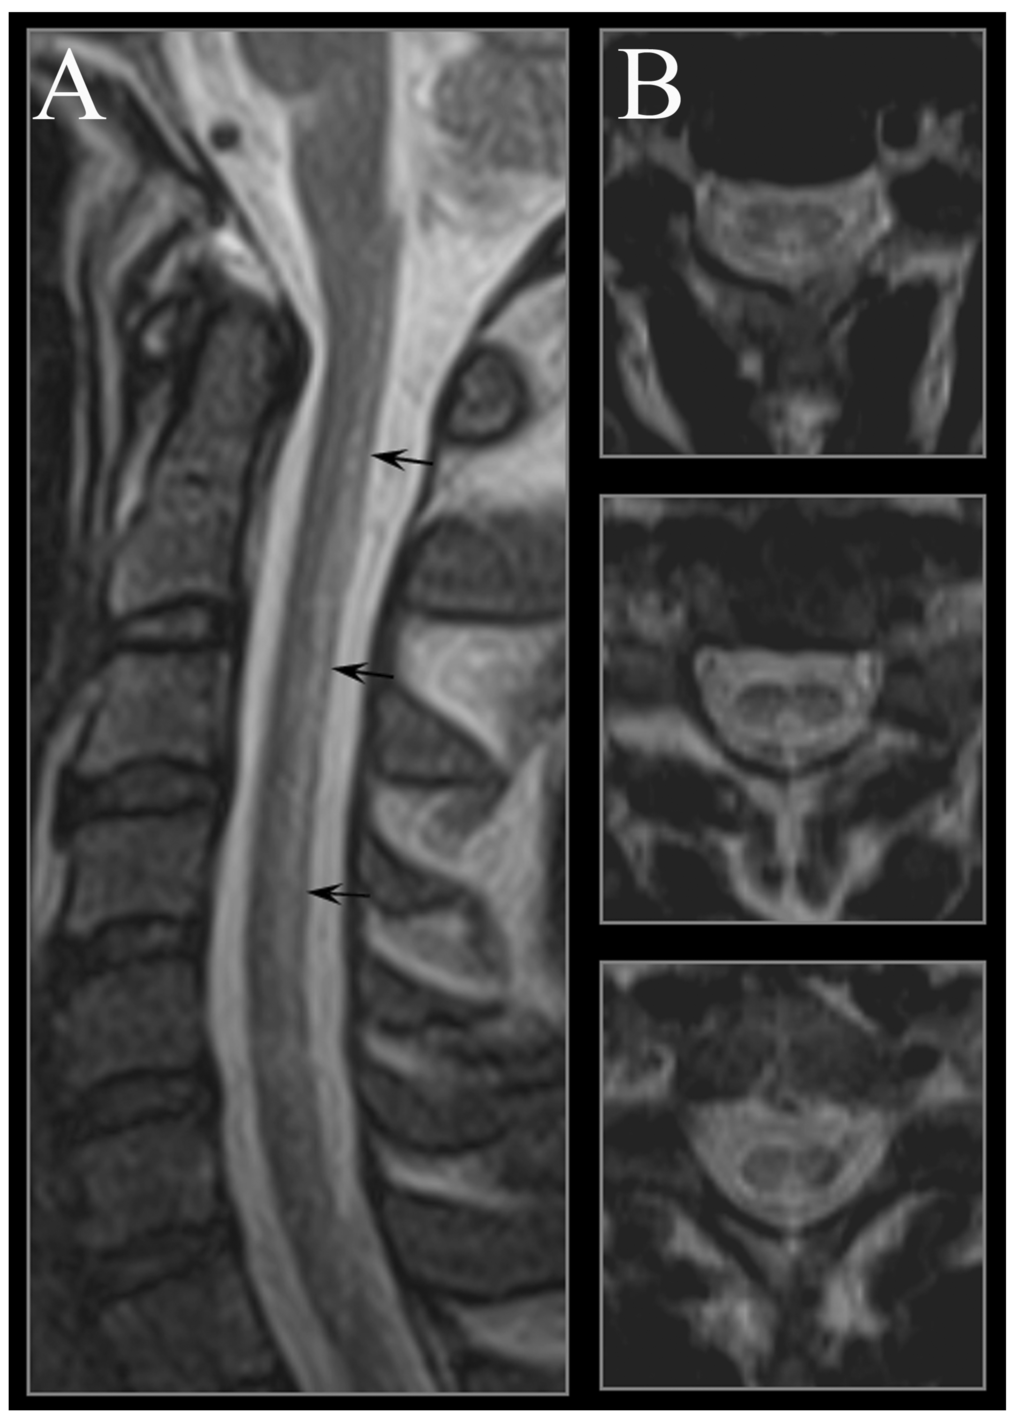

4. Neuroimaging

- Yamada, K.; Shrier, D.A.; Tanaka, H.; Numaguchi, Y. A case of subacute combined degeneration: MRI findings. Neuroradiology 1998, 40, 398–400. [Google Scholar] [CrossRef]

- Timms, S.R.; Cure, J.K.; Kurent, J.E. Subacute combined degeneration of the spinal cord: MR findings. AJNR 1993, 14, 1224–1227. [Google Scholar]

- Tajima, Y.; Mito, Y.; Owada, Y.; Moriwaka, F.; Tashiro, K. MR appearance of subacute combined degeneration of the spinal cord. Jpn. J. Psychiatry Neurol. 1994, 48, 611–614. [Google Scholar]

- Katsaros, V.K.; Glocker, F.X.; Hemmer, B.; Schumacher, M. MRI of spinal cord and brain lesions in subacute combined degeneration. Neuroradiology 1998, 40, 716–719. [Google Scholar] [CrossRef]

- Berlit, P.; Ringelstein, A.; Liebig, T. Spinal MRI precedes clinical improvement in subacute combined degeneration with B12 deficiency. Neurology 2004, 63, 592. [Google Scholar]

- Ravina, B.; Loevner, L.A.; Bank, W. MR findings in subacute combined degeneration of the spinal cord: A case of reversible cervical myelopathy. Am. J. Roentgenol. 2000, 174, 863–865. [Google Scholar] [CrossRef]

- Karantanas, A.H.; Markonis, A.; Bisbiyiannis, G. Subacute combined degeneration of the spinal cord with involvement of the anterior columns: A new MRI finding. Neuroradiology 2000, 42, 115–117. [Google Scholar]